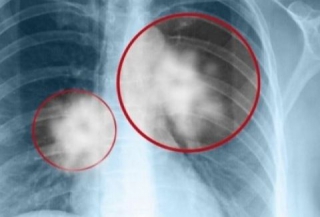

Στο Κέντρο Μοριακής Ανοσολογίας (CIM) στην Κούβα διατίθεται δωρεάν, το πρώτο εμβόλιο στους ασθενείς με καρκίνο του πνεύμονα. Σύμφωνα με τους ειδικούς είναι μια νέα…